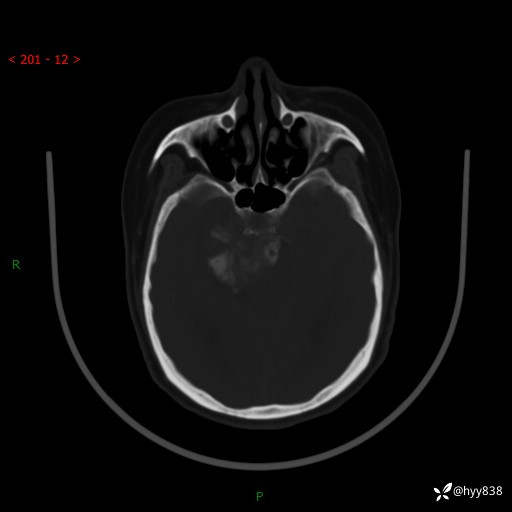

颅脑CT平扫